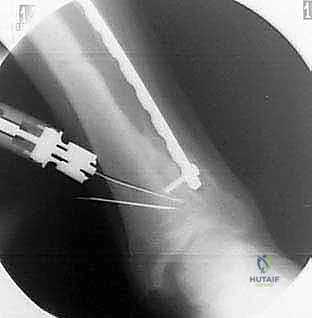

4. قطع العظم (The Osteotomy)

هناك تقنيتان رئيسيتان يختار الدكتور هطيف بينهما بناءً على حالة المريض:

* تقنية الوتد المفتوح (Opening Wedge): يتم عمل شق في العظم وفتحه لإضافة طعم عظمي (صناعي أو من حوض المريض) لتعديل الزاوية.

* تقنية الوتد المغلق (Closing Wedge): يتم إزالة مثلث صغير من العظم، ثم إغلاق الفراغ لتعديل المحور.